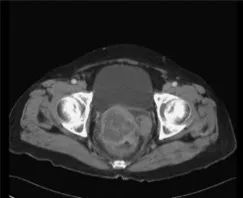

诊断:术前评估包括CT扫描(6.3x5.3cm宫颈肿块,伴有直肠和阴道侵犯)、结肠镜检查(粘膜完整的外部压迫)、肿瘤标记物和活检(梭形细胞瘤)。术后病理确诊GIST。